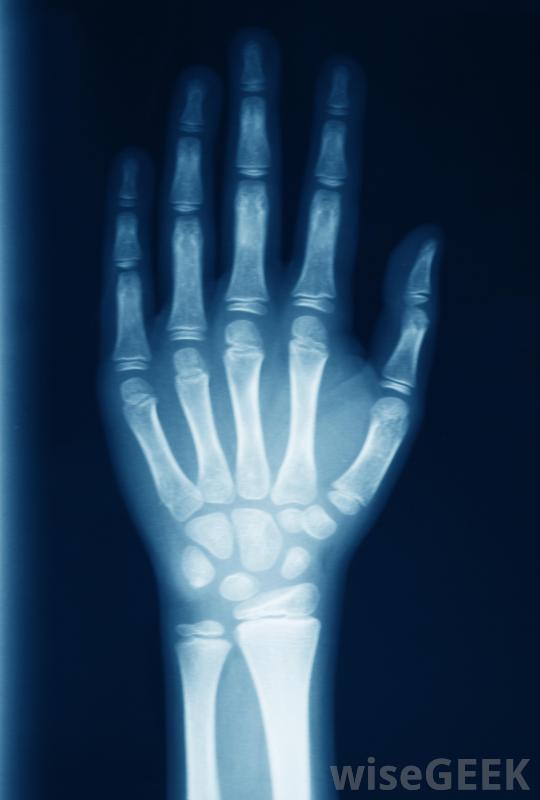

腕關節核磁共振的常見原因是什么(What Common Reasons for a Wrist MRI)?

醫學專家可能會要求對腕關節進行磁共振成像(MRI),以評估近期有外傷、關節不穩定跡象的患者,對于腕關節損傷,MRI檢查是一個比較常見的問題,也是一個關于腕關節損傷的常見原因提前。保險公司會詢問醫生為什么要進行檢查,并可以確定它是否符合他們的保險標準。如果在當腕關節出現腕關節不穩和損傷的跡象時,醫生可能會要求進行影像學檢查,以檢查腕關節的軟組織。腕關節核磁共振成像提供了極好的分辨率和全面的視野案件,它可以省去昂貴的關節鏡檢查韌帶撕裂和其他問題的風險,使其成為非常有用的診斷工具。醫生可能會要求腕關節核磁共振來評估最近有外傷或關節不穩定癥狀的病人。要求做腕關節核磁共振的另一個原因是如果其他影像學檢查發現異常,像x射線或計算機斷層掃描這些可能是在外傷后,如疑似骨折。如果它們顯示出難以準確診斷的問題跡象,醫生可能會要求核磁共振成像以獲得更詳細的信息。這些附加信息有助于診斷,并可能使醫生制定更有效和更合適的治療計劃核磁共振成像機利用磁場和無線電波來生成內部器官和骨骼結構的圖像如果體格檢查顯示存在疾病,包括疑似手腕腫瘤,也可以要求進行此項檢查。缺血性壞死,即血液供應有限導致骨骼或組織死亡,或嚴重關節炎的情況,也可以在手腕MRI的幫助下進行評估。掃描可提供詳細信息關于腕關節內發生了什么,以及在這種情況下最好的治療方法是什么。有慢性、持續性腕關節疼痛、炎癥和其他疾病癥狀的患者可以從腕部核磁共振成像(MRI)中早期發現問題腕部外傷可能使橈動脈搏動難以定位。可要求進行腕部核磁共振成像作為后續治療。例如,手術后,手腕外科醫生可能需要檢查手腕內部,以確定患者是否正在愈合,并評估治療是否成功在癌癥治療的過程中,也可以建議進行影像學檢查,看看癌癥是否對化療和放療有反應,如果有人擔心這種可能性的話,用腕關節核磁共振成像來尋找復發的跡象,這一點也很重要如果懷疑骨折,可以接受手腕MRI檢查。手腕MRI可以幫助診斷手腕疼痛的原因。